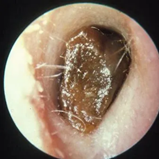

耳垢栓塞

· 患耳部皮肤病(如湿疹)导致耳道皮肤细胞大量脱落,造成耳垢蓄积;

· 耳部损伤严重/多次耳道感染后导致耳道变窄,容易发生耳垢栓塞;

· 耳道进水或耳道局部创伤后,产生了大量超过耳道清除能力的耳屎;

· 天生耳道内毛发过多,将耳屎限制于耳道之内,难以正常排出;

· 耳垢随年龄增长逐渐变硬变稠厚,排出耳道的速度变慢,促使耳垢蓄积;

……

可以看到,出现耳垢栓塞的情况基本都有特定的诱因,不是随随便便就会发生的。